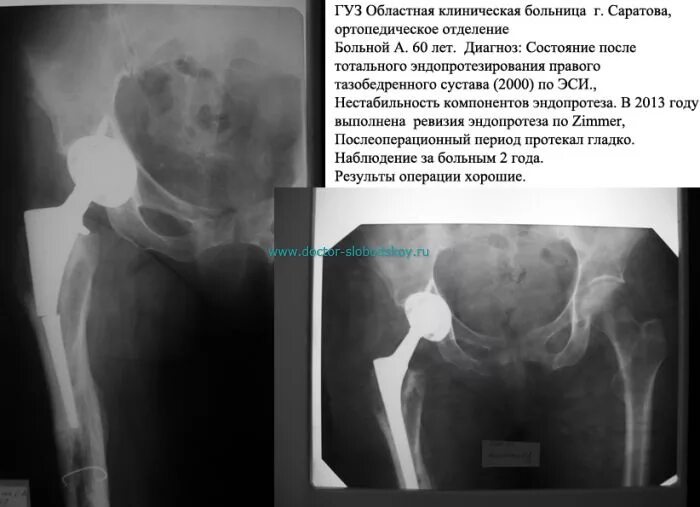

Ревизия тазобедренного сустава